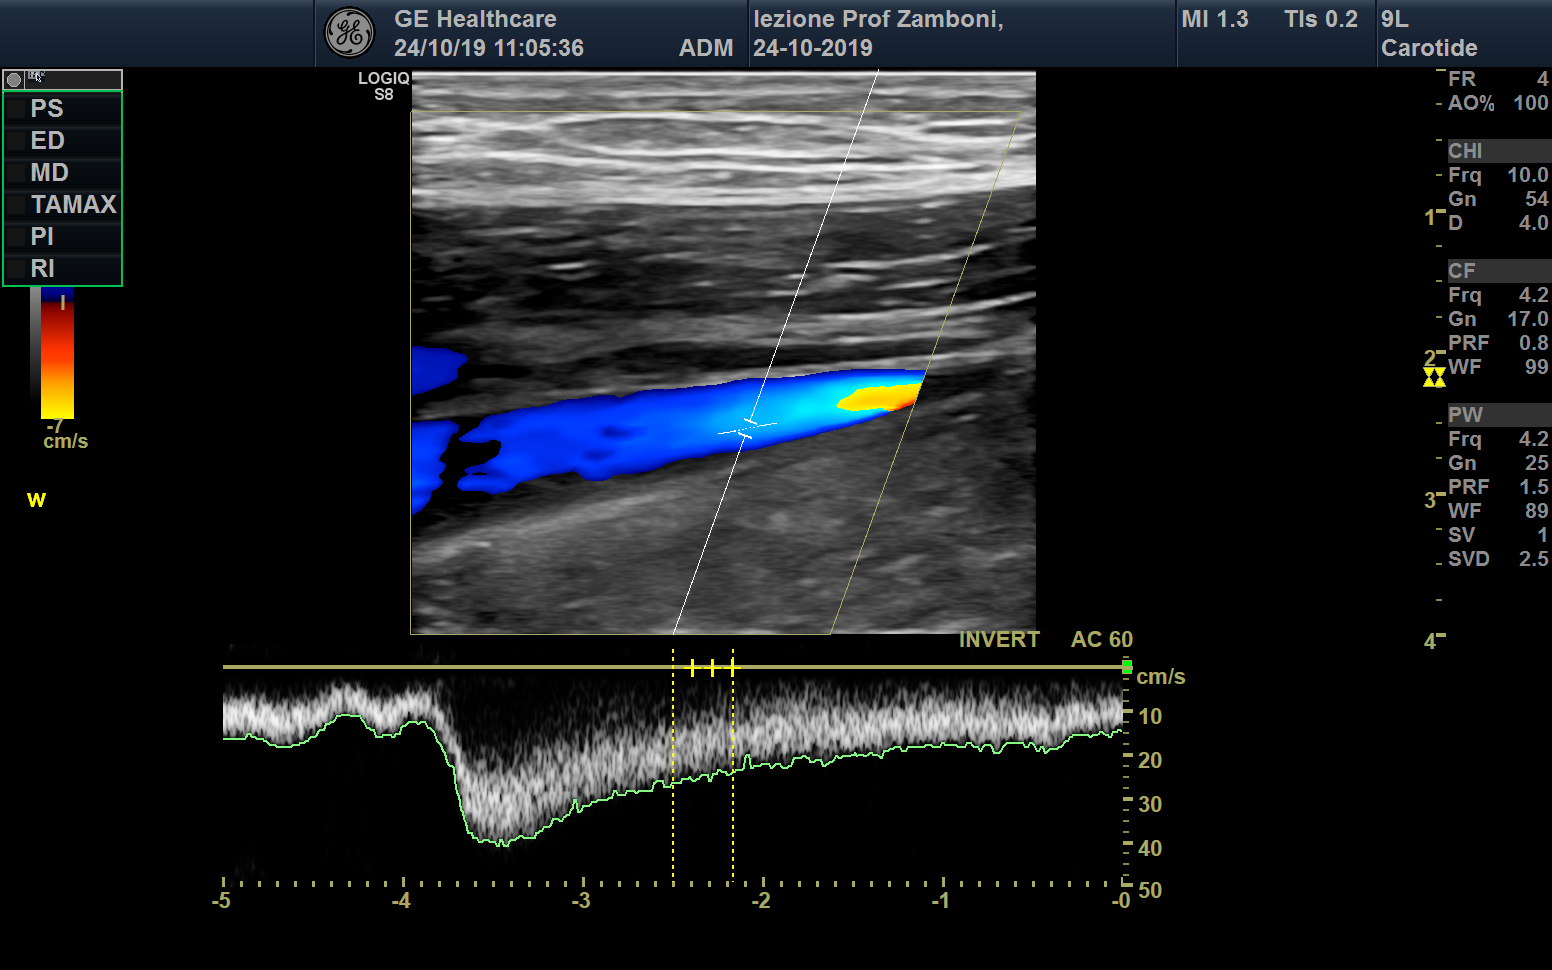

PW V. Femorale wunstorf long

JPEG image icon PW V. Femorale wunstorf long.jpg — JPEG image, 602 kB (617356 bytes)